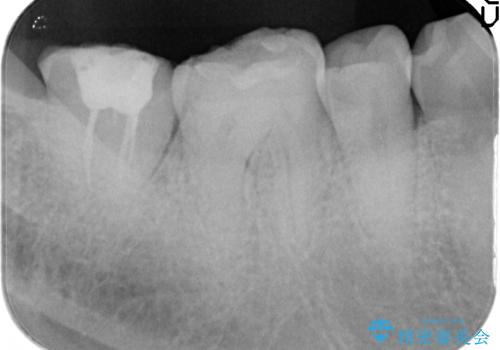

歯ぎしりによる異常に低い歯冠高径 歯周外科による解決

失活歯であるため根管治療ののちクラウン製作が治療計画として考えられますが長年のすり減りによりクラウン高径がほとんどなくてなってしまっている状態です。

あまりにもクラウン高径が低いと、安定性が悪くなりセメントの溢出を招き虫歯の再発リスクを高めます。